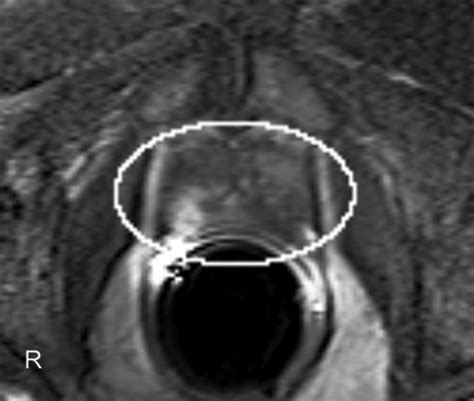

• T2-weighted imaging: Provides high-resolution anatomical images, allowing the radiologist to see the shape and size of the prostate clearly.

Interpreting Results with PI-RADS

After your MRI of prostate is completed, the images are analyzed by a specialized radiologist. They use a standardized reporting system known as PI-RADS (Prostate Imaging-Reporting and Data System). This system assigns a score from 1 to 5 to any suspicious areas identified: